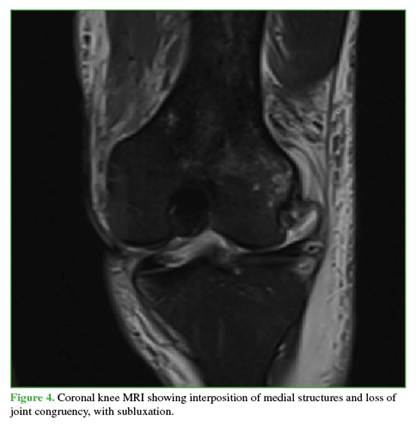

Radiographs showed widening of the medial joint space consistent with medial instability. Further imaging was obtained with magnetic resonance imaging (Figures 4 and 5) to evaluate possible interposed tissues or structures, and with CT angiography (Figure 6) to rule out vascular injury given the time elapsed since trauma. Marked edema was noted in the medial soft tissues, including the capsule and medial structures in the intercondylar region, along with persistent knee subluxation. Vascular compromise was ruled out, with preservation of the femoropopliteal vascular bundle.